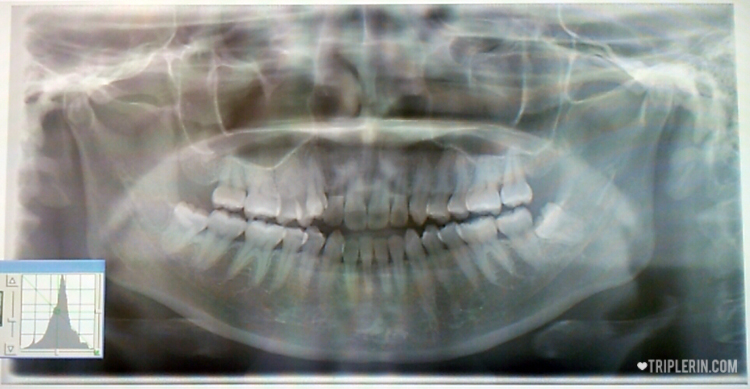

After handing in the forms, a dental assistant who spoke English came to me and explained the procedures. Then I was shown to a room to take my x-ray.

Offending wisdom tooth on the left.

The bad news is I discovered that the wisdom tooth on the right is lying in wait. UGH. And what’s with the slanted growth?!! FML.

After that, I was shown to the treatment room, and the dentist told me that because the wisdom teeth on the bottom row was close to the main nerves in the jaw, she wants me to take a CT scan to see if it’s possible to extract it.